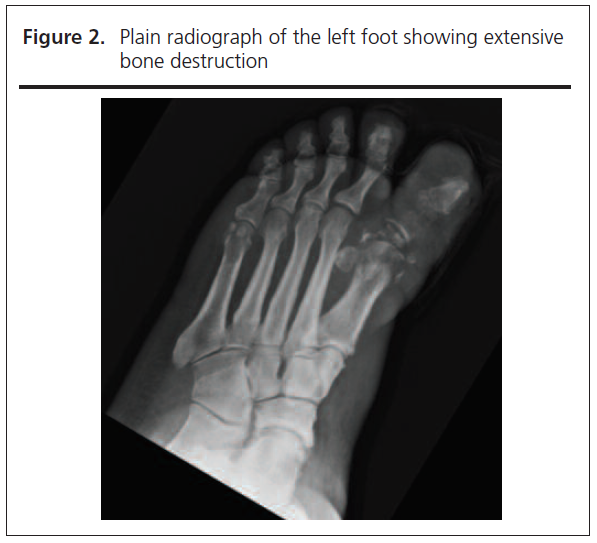

Spinal examination did not reveal any localised tenderness and neurological examination was unremarkable. Blood results on admission showed markedly raised inflammatory markers with a white cell count of 14.9x109/L (neutrophils 12.1x109/L) and a C-reactive protein of 267 mg/L. Plain radiograph of the left foot demonstrated extensive bony destruction of the left hallux (Figure 2), and an MRI scan with contrast confirmed bone marrow oedema extending to the first metatarsal and involving distal tendons of the left hallux, all consistent with osteomyelitis. Time-Resolved Imaging of Contrast Kinetics (TRICKS) suggested significant vascular disease with only the anterior tibial artery being seen, feeding into the dorsalis pedis but not forming a complete plantar arch. There was no evidence of bacteraemia on blood cultures; however, tissue culture from the left hallux isolated coagulase negative Staphylococcus, Streptococcus anginosus and Actinetobacter pittii. Given the ongoing back pain and previous history of spinal osteomyelitis, an MRI scan of the spine was performed which showed discitis with epidural and paravertebral abscess at the level of T9/10 (Figure 3).

Mehta Figure 3